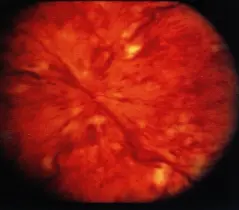

Vitreous hemorrhage

- Profuse preretinal hemorrhage into the vitreous or hemorrhage of retinal neospastic vasculature